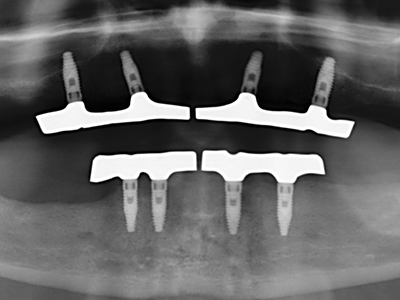

Abb. 11: Das postoperative OPTG veranschaulicht die vertikale Augmentation und Sinusbodenelevation.

Abb. 12: Nach sechs Monaten Heilungsperiode zeigt sich ein in allen Richtungen ausreichend dimensionierter, vitaler Kieferkamm.

Abb. 14: Einbringung von vier konischen RSX-Implantaten (Bego Implant Systems, Bremen).

Abb. 15: Die röntgenologische Ein-Jahres-Kontrolle zeigt stabile Verhältnisse des Knochenniveaus.

Abb. 16: Auch intraoral stabile Verhältnisse mit Einbettung der Implantate in keratinisierter Gingiva.